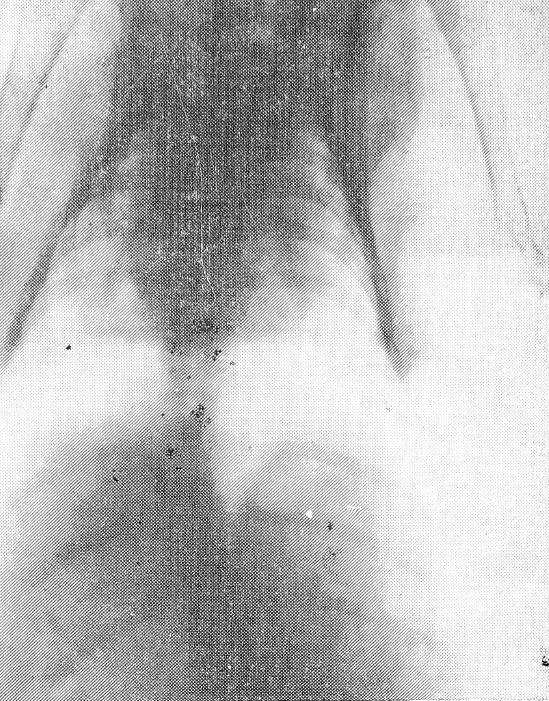

Через 4 месяца на спондилограммах было определено сравнительно медленное дальнейшее увеличение угла искривления (до 30—32°) вследствие замедления темпа роста животного (рис. 3). Прослеживались торсия и клиновидная деформация тел позвонков на вершине искривления, сужение межреберных промежутков с вогнутой стороны.

Рис. 3. Спондилография грудного отдела позвоночника через 4 месяца. С-образный сколиоз III степени